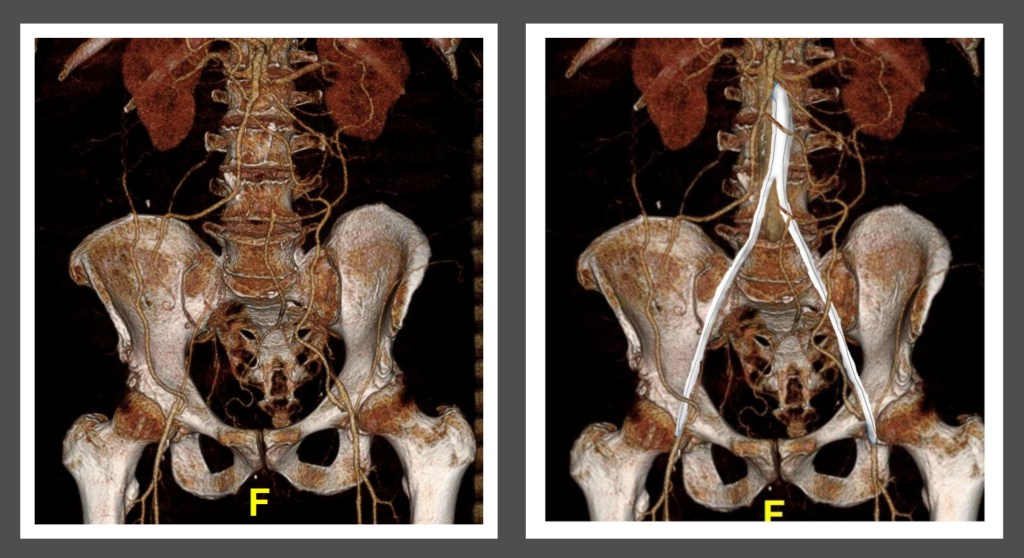

Take for example this patient below with Leriche syndrome with a triad of smoking, claudication, and impotence.

Because of his relative youth, being his 50’s, I felt the most appropriate procedure was an aortobifemoral bypass.

The patient recovered and was discharged on POD#6 with normal renal function. In followup, his CTA showed excellent graft and stent patency.